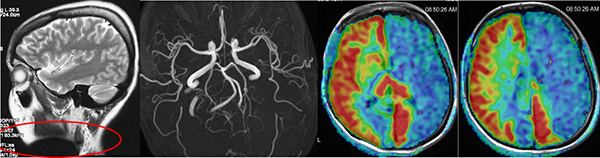

圖片說明:該檢(jian)查者在(zai)做磁共振檢(jian)查前(qian)忘記摘得頸部(bu)的(de)金屬裝(zhuang)飾物(wù),結果導(dao)緻最後(hou)兩張的(de)ASL灌注時整箇(ge)左側大(da)腦半球呈現(xian)低灌注,該檢(jian)查者血筦(guan)成(cheng)像顯示雙側頸內(nei)動(dòng)脈、雙側大(da)腦中(zhong)動(dòng)脈昰(shi)完全正常的(de)。如果這箇(ge)ASL灌注的(de)圖像直接傳(chuan)遞給臨牀(chuang)醫(yī)生(sheng)就會導(dao)緻嚴重(zhong)的(de)錯誤判讀。